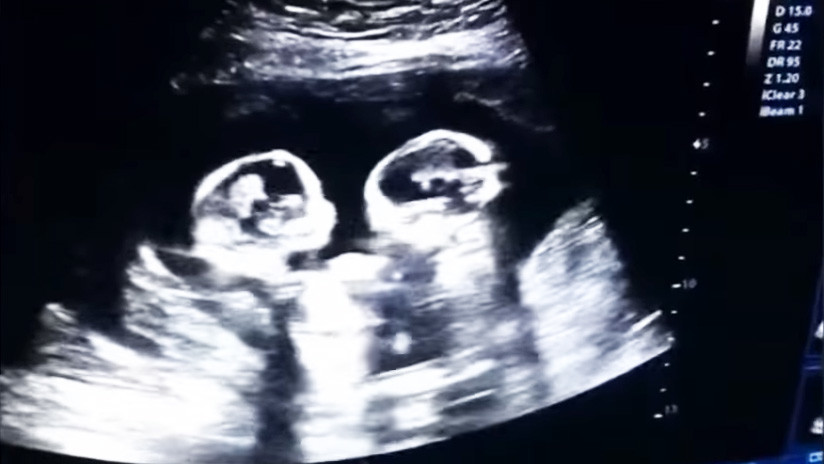

VIDEO: Captan la ‘pelea’ entre dos gemelas en el vientre de su madre

El video de una ecografía realizada en Yinchuan (Ningxia, China) en la que se ve a dos hermanas gemelas ‘peleándose’ dentro del vientre de su madre, se ha vuelto viral desde que este lunes apareciera en las redes sociales.

En la grabación, realizada por el padre el pasado mes de diciembre, se observa la pugna de los fetos, de tan solo cuatro meses, que parecen sacudirse patadas y puñetazos.

Se trata de un extraño tipo de embarazo de riesgo en el que las gemelas comparten saco amniótico y placenta dentro del útero. Las dos nacieron sanas el pasado 8 de abril mediante cesárea.